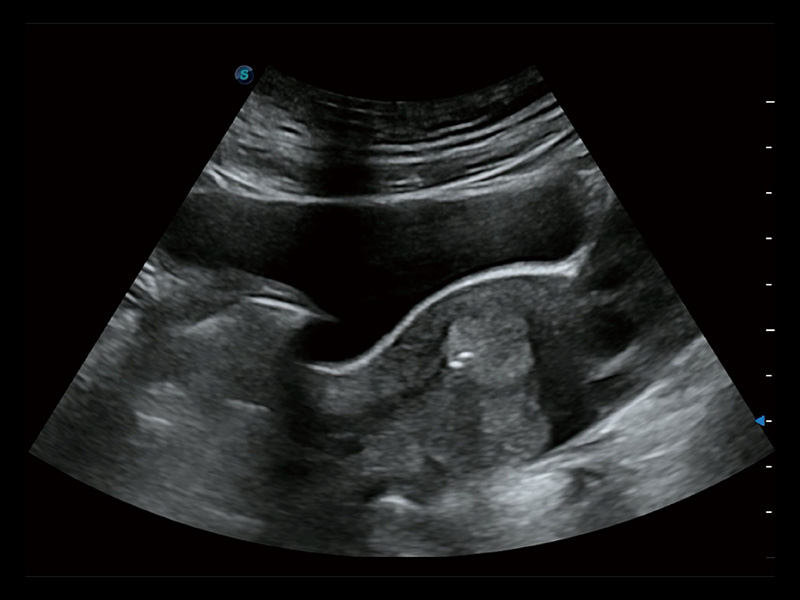

“生育问题”即关系民族复兴,也关系亿万家庭的幸福。随着婚育年龄推迟、社会压力增加等因素,越来越多人群也面临着“生不出、生不好”的问题。辅助生殖作为治疗不孕不育最有效的方法之一,也逐渐成为育儿新希望。而超声检查能为生殖需求人群的初诊评估提供宝贵的信息。 P20 Elite是哈哈体育官网匠心打造的一款生殖应用型彩超。她继承哈哈体育官网高端极光平台,突破性地将多款新型芯片及硬件模块进行整合,均衡了高端系统性能与小巧灵动机身。P20 Elite卓越的图像质量搭载专科探头,旨在为您提供全面的辅助生殖解决方案。

P20 Elite配备了丰富的生殖探头群和临床应用功能,在卵泡监测、穿刺取卵、胚胎移植、妊娠确认等领域,为生殖需求人群提供了新的临床机会,重新定义高端超声如何应用于生殖健康检查。